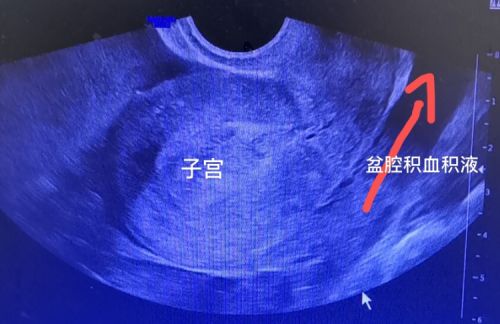

盆腔大量积液。

7月20日上午,22岁的小雨忽然下腹部剧烈疼痛、头晕、乏力、面色苍白,由母亲搀扶紧急送至捷克论坛 天心阁院区。妇科黄薇主任接诊后,立即为她做了尿妊娠检查,结果为阳性;腹部+妇科B超提示:子宫与卵巢之间有一个鸡蛋大小的包块;盆腹腔有大量积液;阴道后穹隆穿刺抽出8ml暗红色不凝血,考虑为“异位妊娠破裂出血,失血性休克”。